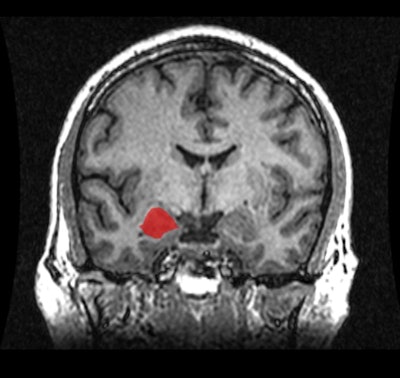

The amygdala is associated with emotion and social behavior such as aggression and sexual arousal. Animal studies and early MRI research indicated that the amygdala is disproportionately larger in males' brains. It has been suggested that the difference in size contributes to gender differences in emotionality and in the prevalence of disorders such as anxiety and depression.

The results showed that the amygdala was approximately 10% larger in male brains; however, the difference was comparable to males' larger body size, including the 11% to 12% larger volume of their brains overall. Among studies that adjusted for overall brain size, the volume difference was less than 0.1% in the right amygdala and 2.5% in the left amygdala, both of which were not statistically significant.